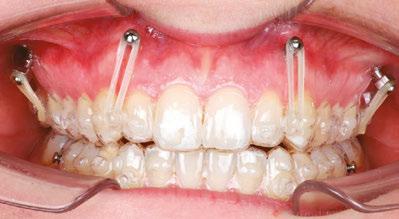

Maintain CL I occlusion. Develop the transverse relationships, eliminate the posterior negative root torques, and resolve the excessive gingival display via full-arch nonsurgical impaction. All vertical changes would be accomplished using only Angel Aligner, TADs, and elastics. Her maxillary lateral incisors may later require buildups to improve the Golden Proportion of the anterior teeth. My iOrtho software setup for maxillary intrusion was to place angelButtons (blue) between the U2s-3s, U4s-5s, and distal of the U6s (Figure 4).

My TAD placement protocol involved placing four TADs in the maxilla: two interradicular in the anterior and two infrazygomatic (IZC) in the posterior. The 2 mm x 12 mm IZC TADs were placed extra alveolar, so there was minimal risk for root impingement (Figure 5). Anteriorly, the 1.4 mm x 6 mm interradicular TADs were placed between the roots of the U2-3s, so greater care was required.

Figure 4: My iOrtho virtual setup for Case 1. Note: This case was planned before virtual roots were available

Figure 6: The biomechanics of Intrusion: The iatrogenic labial crown torquing effect of maxillary intrusion

and moments are the key players in tooth movement. Forces are always “visible,” but moments must continually be “envisioned.” Elastics pull from TADs to bonded buttons creates both vertical and horizontal forces, which can lead to iatrogenic moments that cause labial crown torquing.

To manage this phenomenon, practitioners must employ additional mechanics. Some might choose to bond segmented wires occlusally and lingually; others might place additional TADs positioned labially and lingually for sling elastics worn over the occlusal surfaces. Since this was my first Angel Aligner gummy smile case, I designed and had fabricated a customized TAD-anchored palatal appliance to counter any unwanted crown torquing. Thankfully, this appliance did not need to be employed because of the integrated angelButtons and the inherent deflection-resistant properties of Angel Aligner.